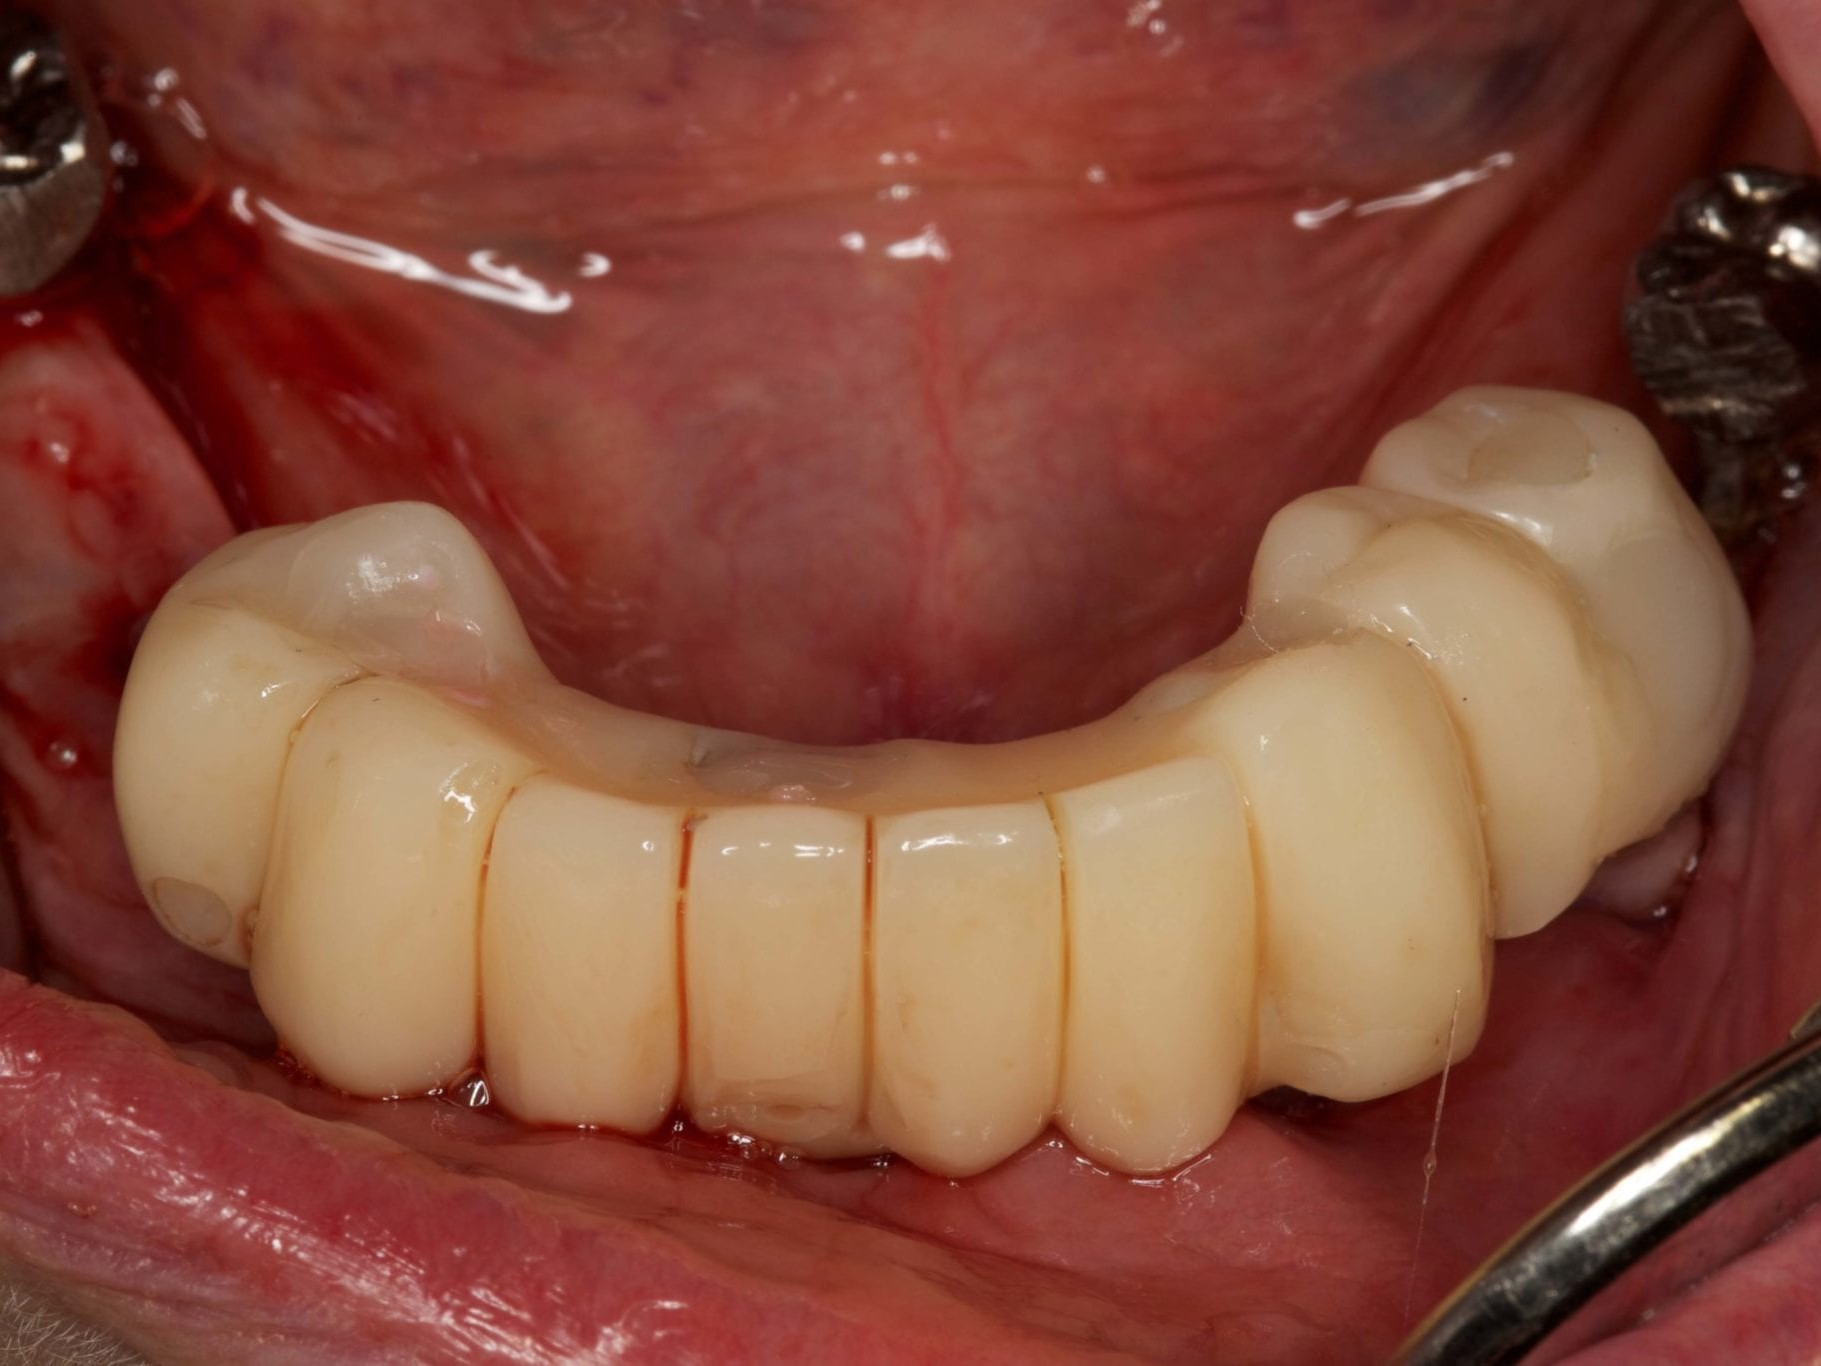

Für die Allgemeinanästhesie erfolgte zunächst die zusätzliche Gabe eines typischen Infiltrationsanästhetikums. Intravenös wurde unmittelbar präoperativ das Antibiotikum Clindamycin 600 mg gegeben. Abbildung 7 zeigt die klinische Ausgangssituation linksseitig. Nach der vorsichtigen Durchtrennung der Brückenkonstruktion (Abb. 8) jeweils vor der Krone auf den Blattimplantaten und Entfernung der nicht erhaltungswürdigen Zähne 44 bis 33 samt ihrer Überkronung (Abb. 9) wurde der Mukoperiostlappen vestibulär wie lingual passend zur erstellten Schablone präpariert und die Bohrschablone in ihrer finalen Lage eingebracht (Abb. 10). Zunächst erfolgte die Insertion der angulierten Implantate Ankylos ® C/X-Implantate (Durchmesser 3,5 mm) der Länge 14 mm in regio 034 (Abb. 11 und 12) und 044. Danach wurden in den Positionen 032 und 042 jeweils ein weiteres Ankylos ® C/X –A-Implantat mit gleicher Länge und Durchmesser inseriert (Abb. 13). Sämtliche entfernten Knochenpartikel und auch Bohrspäne wurden akribisch asserviert. In den Positionen 032 und 042 wurden Ankylos ® Balance Basisaufbauten C/ (GH 3,0 / Ø 5,5 mm, Kopfhöhe 2,4 mm) mit 15 N/cm eingeschraubt. Anschließend hat der Zahntechniker mittels der Ankylos ® Modellierhilfskappenfür den Balance Basisaufbau Retentionskappen hergestellt, die mit 25 N/cm eingebracht wurden (Abb. 14). Am Implantat regio 042 wurde der Knochen in Schalentechnik nach vestibulär aufgebaut (Abb. 15)⁹,¹⁰. Im nächsten Schritt haben wir die angulierten Ankylos ® Balance Basisaufbauten C (nicht indexierte Abutments) in Regio 034 und 044 (GH 3,0, A30 / Ø 4,2 mm, Kopfhöhe 1,3 mm) ausgerichtet und ihren spezifischen Vorgaben entsprechend eingebracht (Abb. 16). Nachdem sich alle erforderlichen prothetischen Implantatbauteile in situ befanden (Abb. 17), erfolgte die Überprüfung und geringfügige Anpassung des im Vorfeld digital erstellten Sofortprovisoriums. Im Anschluss wurden die leeren Alveolen und Knochendefekte mit dem gewonnenen autologen partikulären Material aufgefüllt. Dann erfolgte der typische Naht-Wund-Verschluss mit Einzelknopfnähten eines resorbierbaren Nahtmaterials (Abb. 18). Nachdem die Patientin aus der Vollnarkose erwacht war und ihre motorischen Fähigkeiten wiedererlangt hatte, wurde das Sofortprovisorium eingesetzt und in Okklusion gebracht. In dieser Position wurden die Retentionskappen über ein selbsthärtendes fluoreszierendes kaltpolymerisierendes Paste-Kartuschensystem fixiert. Anschließend erfolgte die extraorale Versäuberung des Interimszahnersatzes. Nach Refixierung des Sofortprovisoriums in der Mundhöhle (Abb. 19 und 20) und dem Verschluss der Schraubenkanäle mit Kunststoff erfolgte die radiologische Kontrolluntersuchung (Abb. 21).